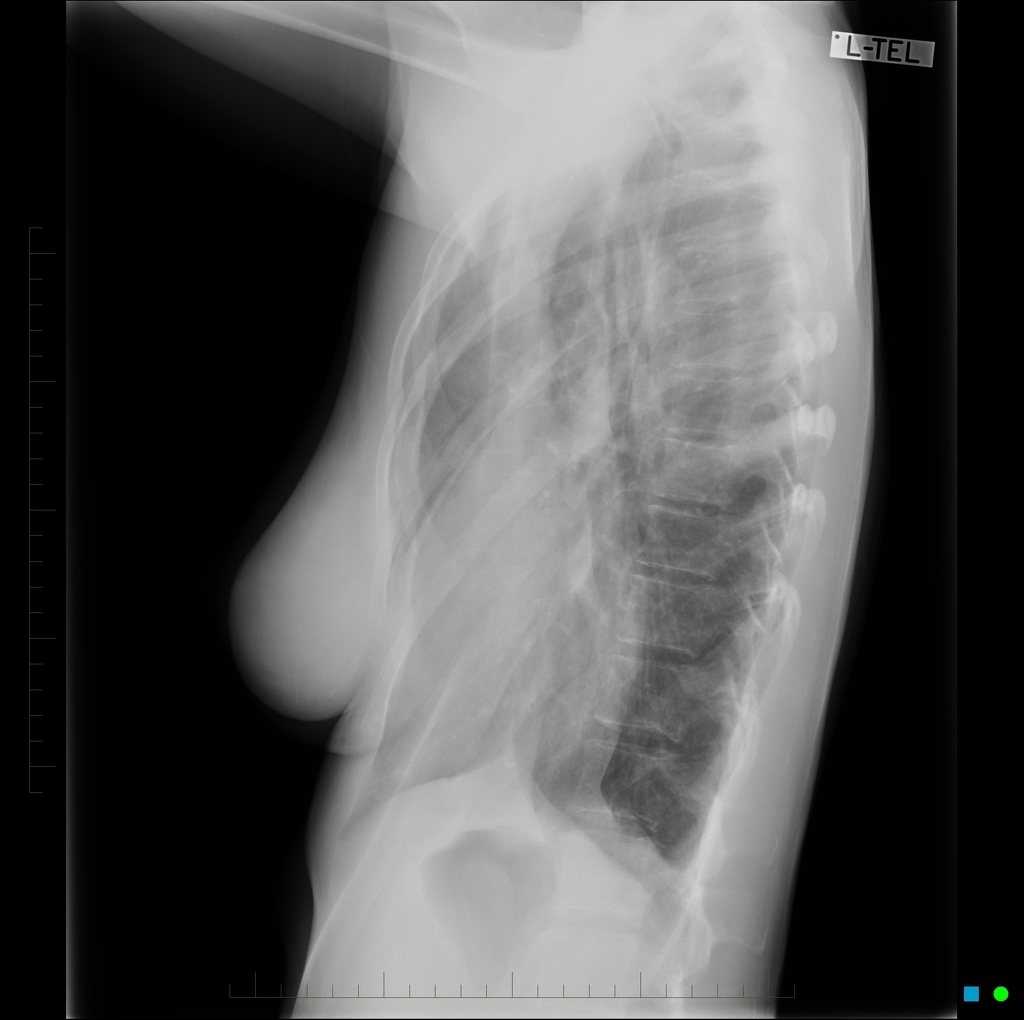

HOMEM DE 20 ANOS COM QUADRO DE INSUFICIENCIA RESPIRATÓRIA E HEMOPTISE. NEGA FEBRE

OPACIDADES DIFUSAMENTE DISTRIBUÍDAS, COM PADRÃO SUGESTIVO DE PREENCHIMENTO ALVEOLAR, PREDOMINANTE EM LOBO INFERIOR DIREITO

HEMORRAGIA ALVEOLAR